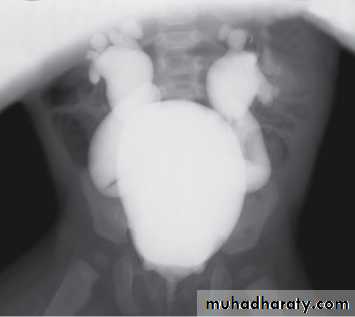

Grading of VUR

The degree of reflux is graded I–V.Grading is based on the appearance of contrast agent in the collecting system during voiding cystourethrography (VCUG(.

The VCUG:

the definitive examination

to diagnose and grade reflux and establish reversible causes

must include a voiding phase:

in some cases, reflux may be seen only during the elevated intravesical pressures associated with micturition.

MCUG